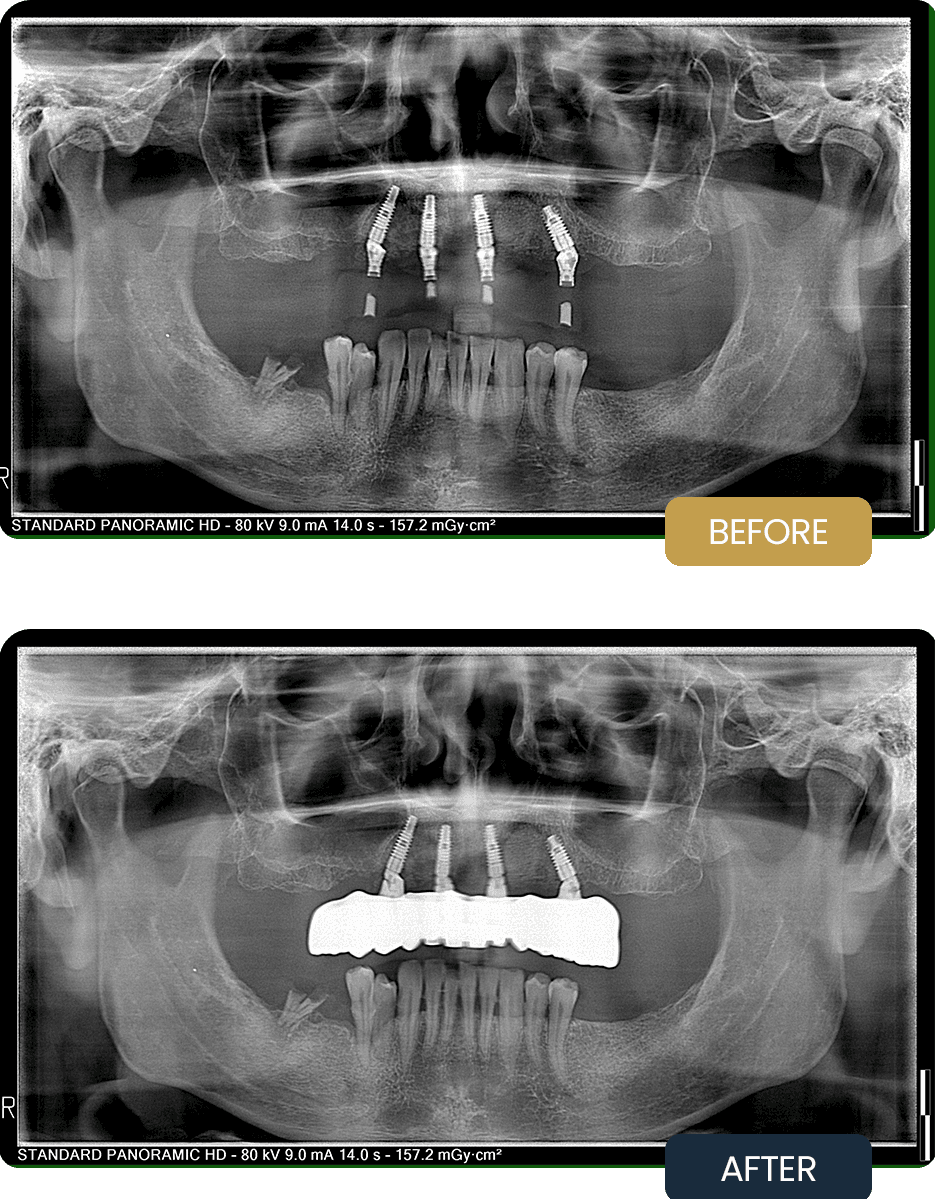

At initial presentation, Alan exhibited advanced tooth loss and compromised bone quality in the upper jaw, affecting both function and comfort. Radiographic assessment revealed the presence of a cystic lesion, necessitating surgical removal prior to final rehabilitation.

The pre treatment panoramic image illustrates the reduced bone support and underlying pathology that required a carefully planned surgical and restorative approach.

Post treatment panoramic imaging confirmed successful integration of all four implants in the upper jaw following cyst removal and bone grafting. The implants demonstrated stable positioning and readiness for final prosthetic loading.

The completed rehabilitation restored chewing function, stability, and overall oral comfort, providing a durable and long term solution designed around precise surgical planning and controlled healing.